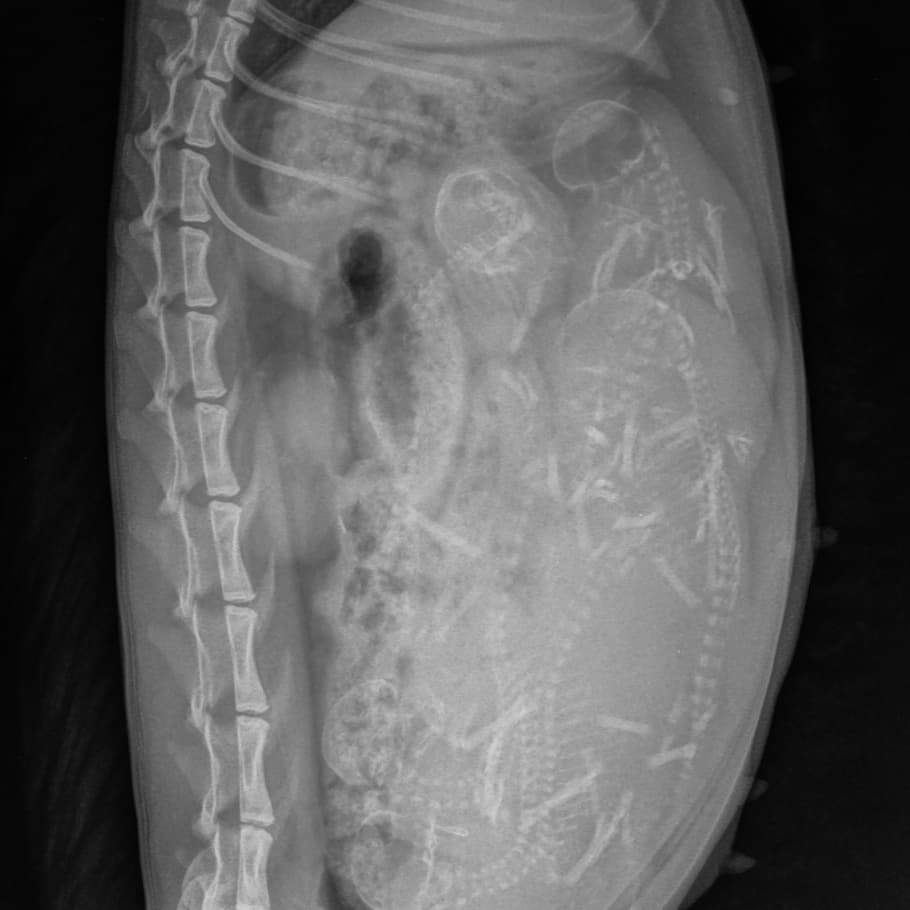

06-04-2021